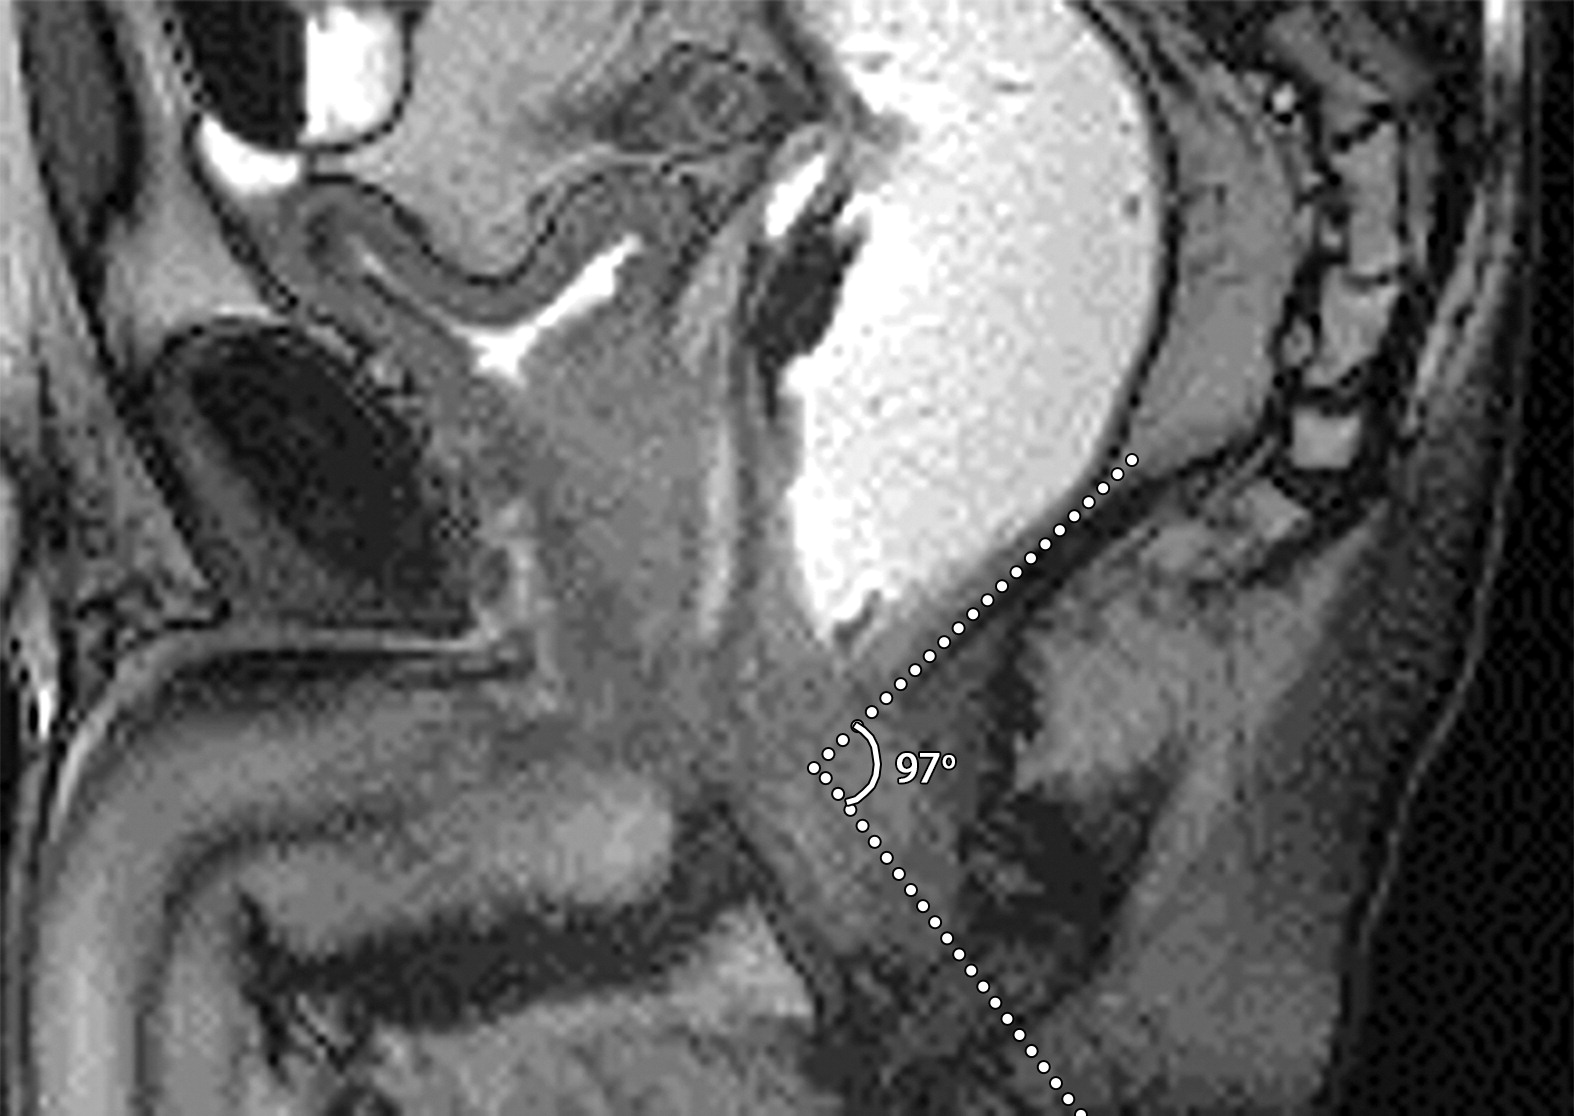

02b30ed4a7e2f5b218cd7c859419af04.jpegd7d20971f4726c22874ec1f489d536ad.jpeg6a942d5d2d6e82f6400de4b653353430.jpeg63岁男性的肛门直肠角。

(a)矢状位T2WI示肛门直肠角,即肛管中轴与远端直肠后壁之间的夹角为87°(白色点状虚线)。男性静息时正常角度约101°(图片未显示)。

(b)矢状位T2WI示提肛板(b图黑色长箭头)在增加腹压过程中正常抬高,导致肛门直肠角下降至68°。

(c)矢状位T2WI示肛门直肠角在紧张和排便期间预期增加到97°。